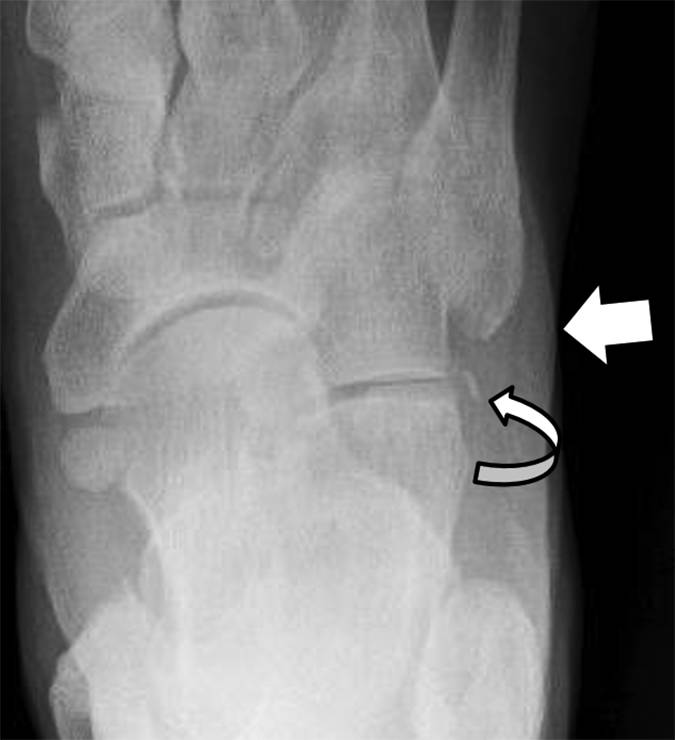

图3 -患者59岁,1型跟骨骨折,症状急性后足跟疼痛。 侧面放射照片显示优越位移的骨片(弯曲的箭头)和跟部结节的上部方面的供体位点缺陷(直箭头)。